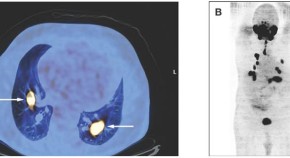

• Poorly differentiated thyroid cancers (PDTCs) are usually aggressive tumors with high rates of recurrence and distant metastases that are often resistant to radioactive iodine therapy. Tuttle and colleagues present the case of a 55-year-old man who was diagnosed with metastatic PDTC and was managed with radioactive iodine therapy. The authors discuss the current management options for patients with PDTCs that are nonresponsive to RAI therapy and highlight the need for the discovery of new systemic treatments for these patients.